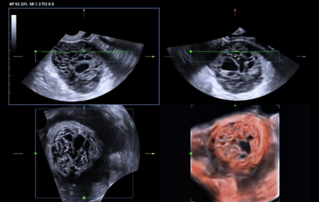

![pericardio-amniotic-shunting-fetal-intrapericardial-teratoma.thumb.319.319 Ultrasound Journal 38 - Pericardio-Amniotic Shunting for Fetal Intrapericardial Teratoma]() Ultrasound Journal 38 - Pericardio-Amniotic Shunting for Fetal Intrapericardial TeratomaLearn how ultrasound-guided fetal therapy saved a fetus with intrapericardial teratoma. Detailed case study of pericardiocentesis and shunt placement with Mindray imaging technology.Patient safety | Ultrasound Cases | Ultrasound | Women health | Cardiology | OB GYN 2025-11-19

Ultrasound Journal 38 - Pericardio-Amniotic Shunting for Fetal Intrapericardial TeratomaLearn how ultrasound-guided fetal therapy saved a fetus with intrapericardial teratoma. Detailed case study of pericardiocentesis and shunt placement with Mindray imaging technology.Patient safety | Ultrasound Cases | Ultrasound | Women health | Cardiology | OB GYN 2025-11-19 -